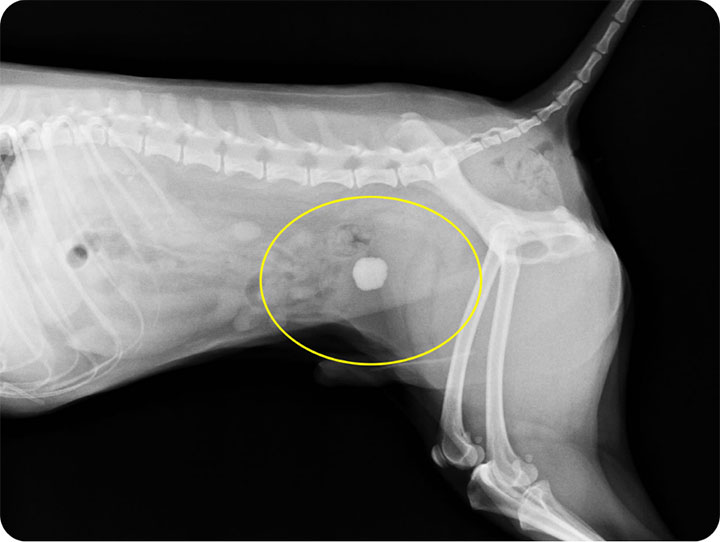

レントゲン検査(単純X線)

カルシウムを多く含む結石(シュウ酸カルシウムなど)はレントゲンに白く写るので、結石があるかどうかを調べられます。ただし、とても小さな結石や、レントゲンに写りにくいタイプの結石は見逃されることがあります。

猫の尿管結石で特に多いのは、以下の2種類です。

シュウ酸カルシウム結石

猫の尿管結石の45%を占める最も一般的なタイプです。非常に硬く、お薬で溶かすことはできません。レントゲンに白くはっきり写ります。